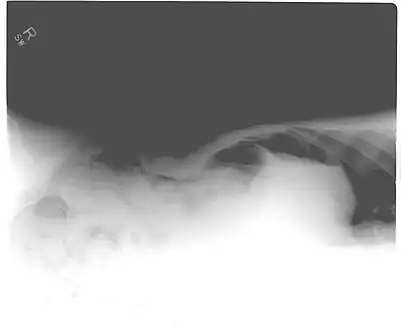

Another pneumoperitoneum on chest X-ray.

Pneumoperitoneum seen on X-ray with the patient lying on his left side.